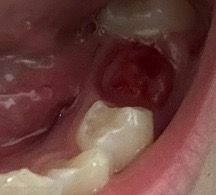

어금니 치아가 빠졌는데 잘 빠진건가요?

왼쪽 두번째 어금니가 빠졌어요,, 흔들리다가 빠져서 혹시 영구치인가요? 또는 잘못빠졌나요 ㅠ 치아가 잘 빠진거맞겠죠?? 알려주세요

유치는 영구치가 나오면서 치아의 뿌리가 녹게되면서 흔들리게 됩니다. 사진상으로는 발치가 잘된것같습니다.

사진 상 치아는 유치가 맞습니다. 치아는 잘 빠진 것으로 보이니 너무 걱정하실 필요는 없습니다.

사진으로 봤을 경우에는 유치의 뿌리가 잘 흡수된 상태에서 안정적으로 빠진 것으로 보입니다. 크게 문제는 없을 것으로 생각되나 영구치아가 정상적으로 맹출되는 것을 확인하기 위해서는 저는 치과에서 진료를 받아봐야 합니다.

네 사진상 잘 빠진 것으로 보이며, 발치부위에 염증이 덧나지 않도록 헥사메딘 가글액으로 가글하여 관리를 하길 권하며, 만약 붓기, 통증, 악취 및 발열 이 발생시에는 염증이 덧난것일 가능성이 높기에 치과를 바로 방문하길 권합니다.